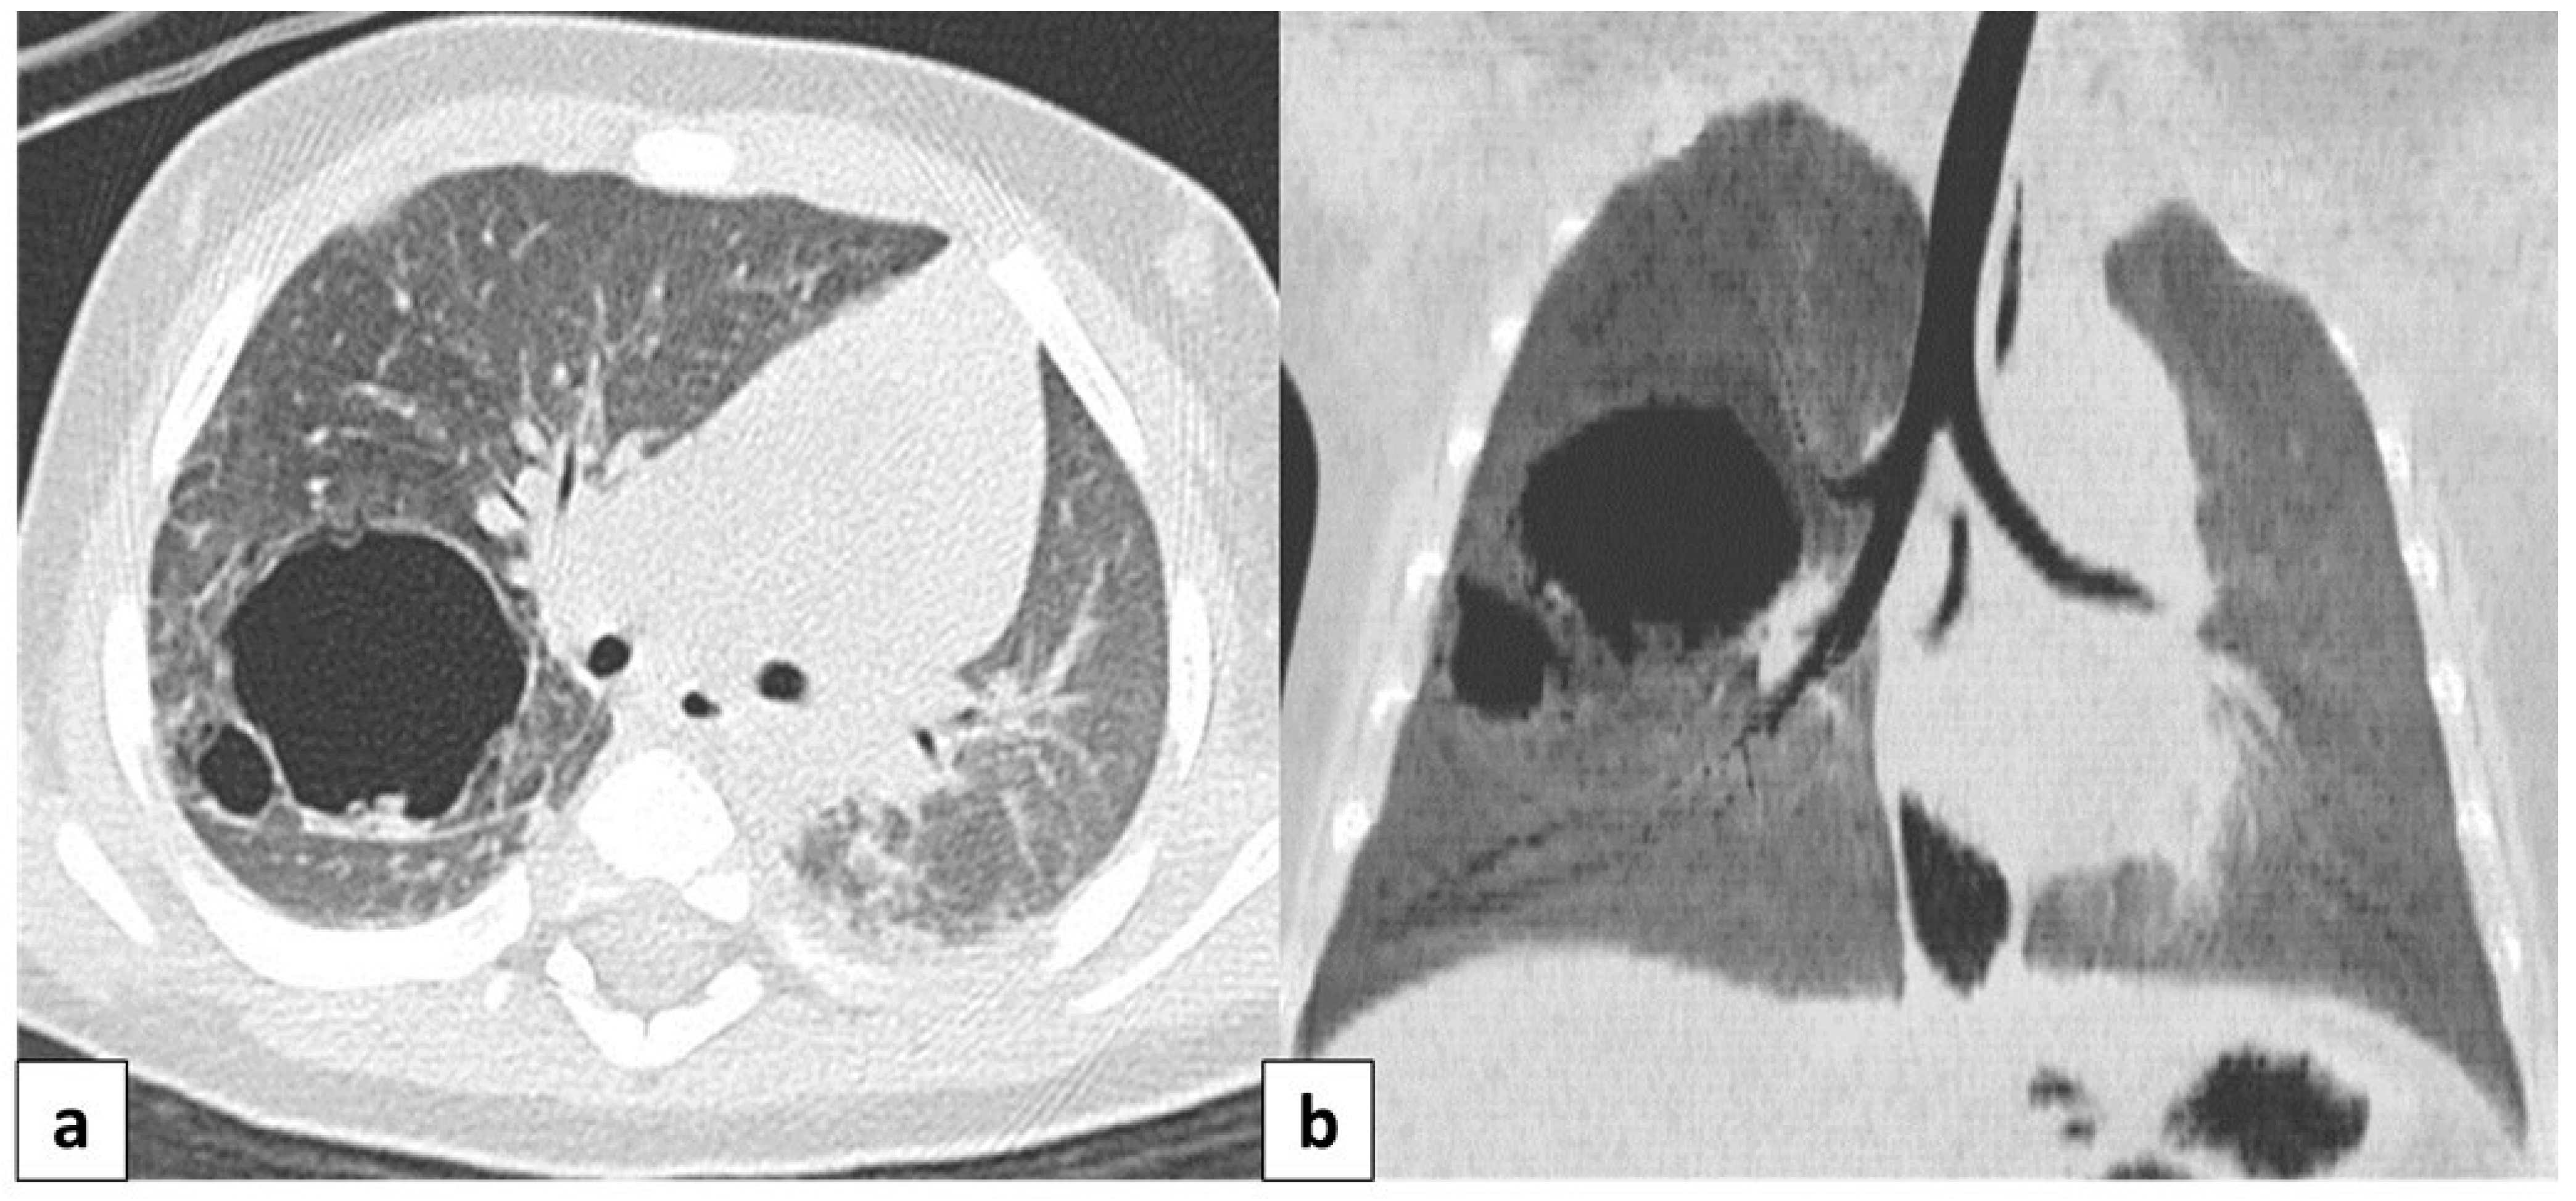

3.6.1. Pulmonary Sequestration

3.6.2. Hypogenetic Lung Syndrome